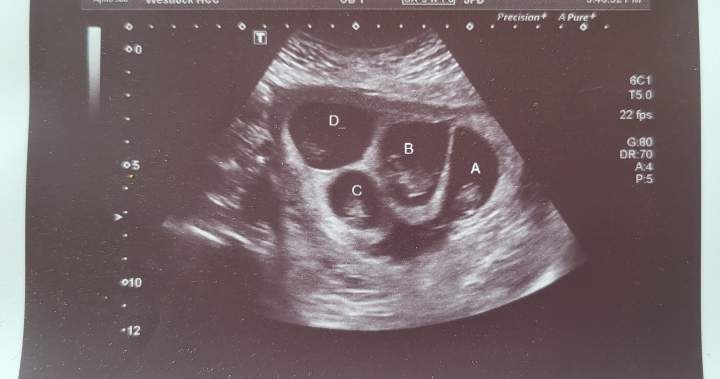

She is currently six months pregnant with quadruplets, three boys and one girl. When she found out, she was shocked.

Darlene Hensch shows off her quadruplet baby bumps.

Provided by: Darlene Hensch